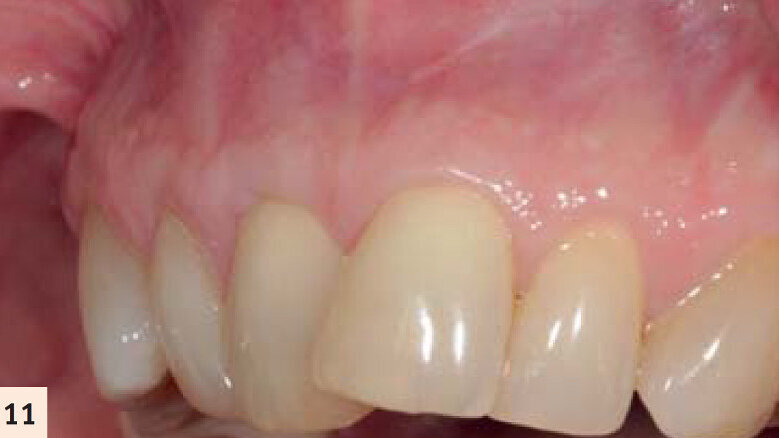

figure 11 : Vues pré- et postop (2 ans). Noter l’augmentation tridimensionnelle de la zone de tissu kératinisé et attaché, ayant pour résultat la restauration de la perte d’attachement et la correction de la

déformation gingivale en hauteur et en largueur.